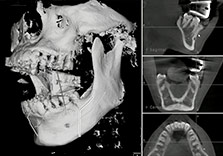

Хувь хүний онцлогт тааруулсан мэс заслын үр дүнг урьдчилан төлөвлөнө.

Өмнө нь мэс заслын үр дүнг 2D ээр урьдчилан эрүүний ясыг зөв байрлалд оруулах хэмжээг тооцоолдог тул тодорхой хэмжээг тооцоолоход мэдээж хэцүү. Navigation эрүүний гажиг засах мэс засал нь үр дүнг бодитоор зөвлөгөө авах үед үр дүнг мэдэх боломжийг өгнө.